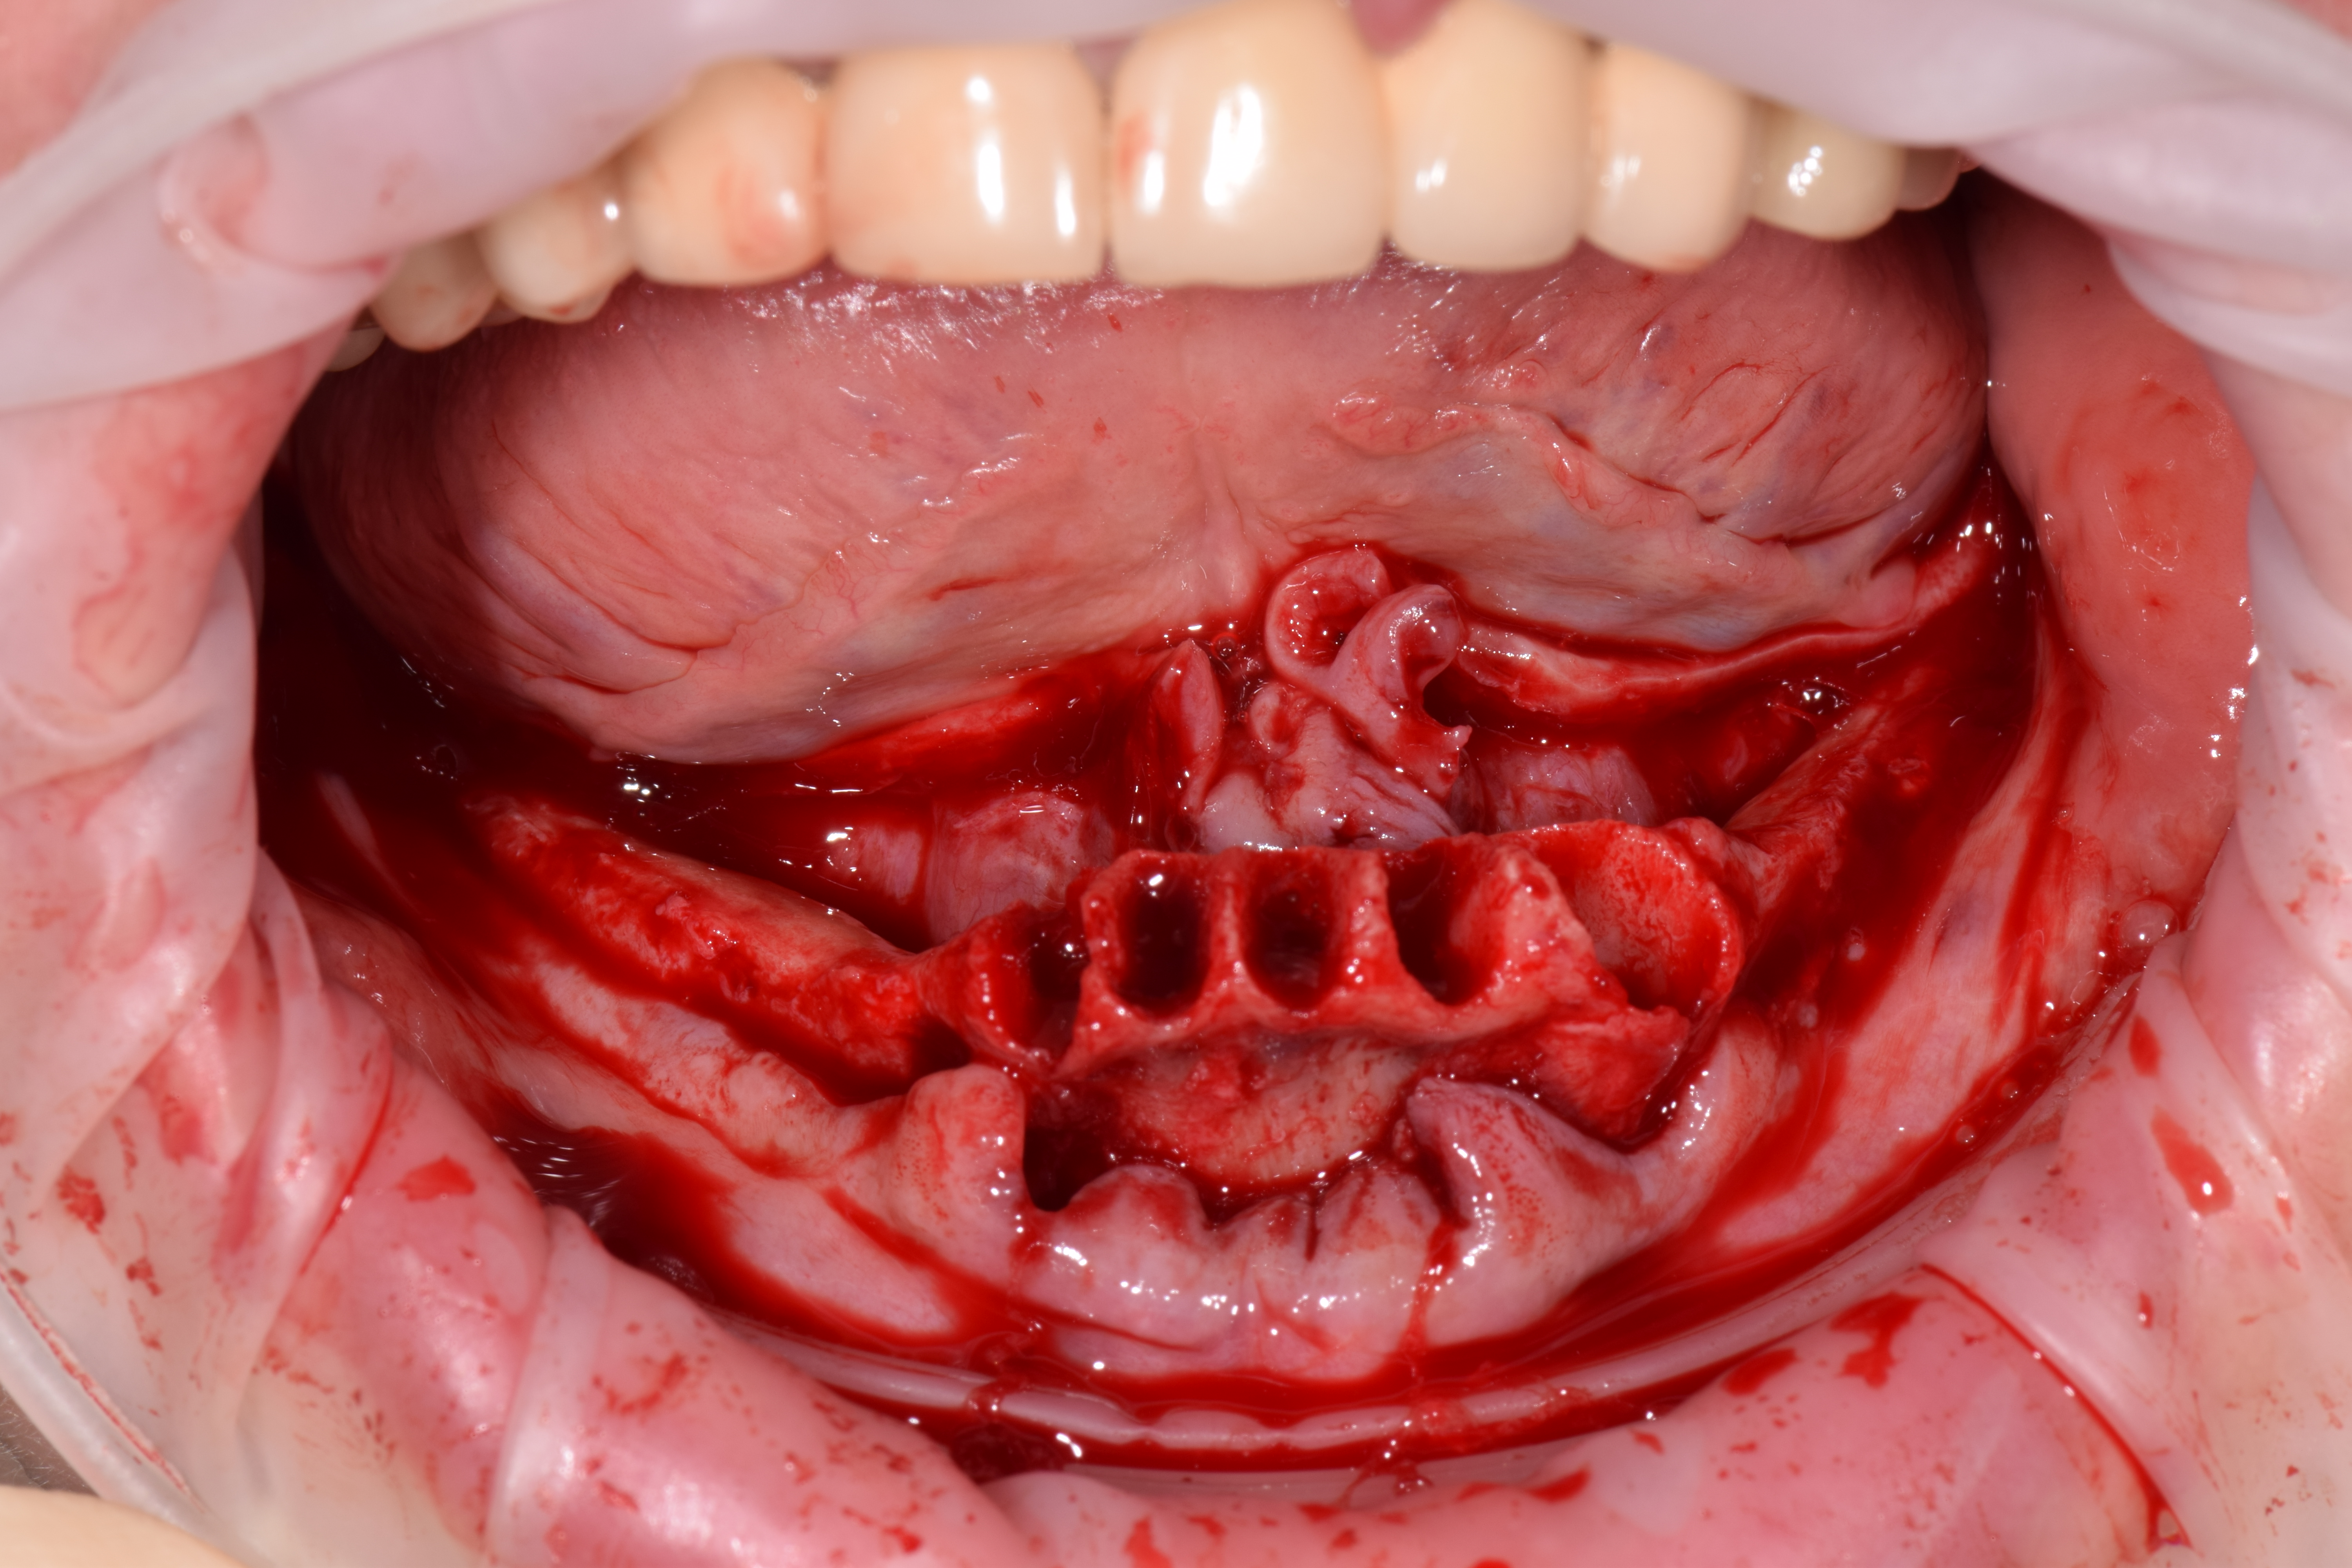

| УДАЛЕНИЕ |

|

|